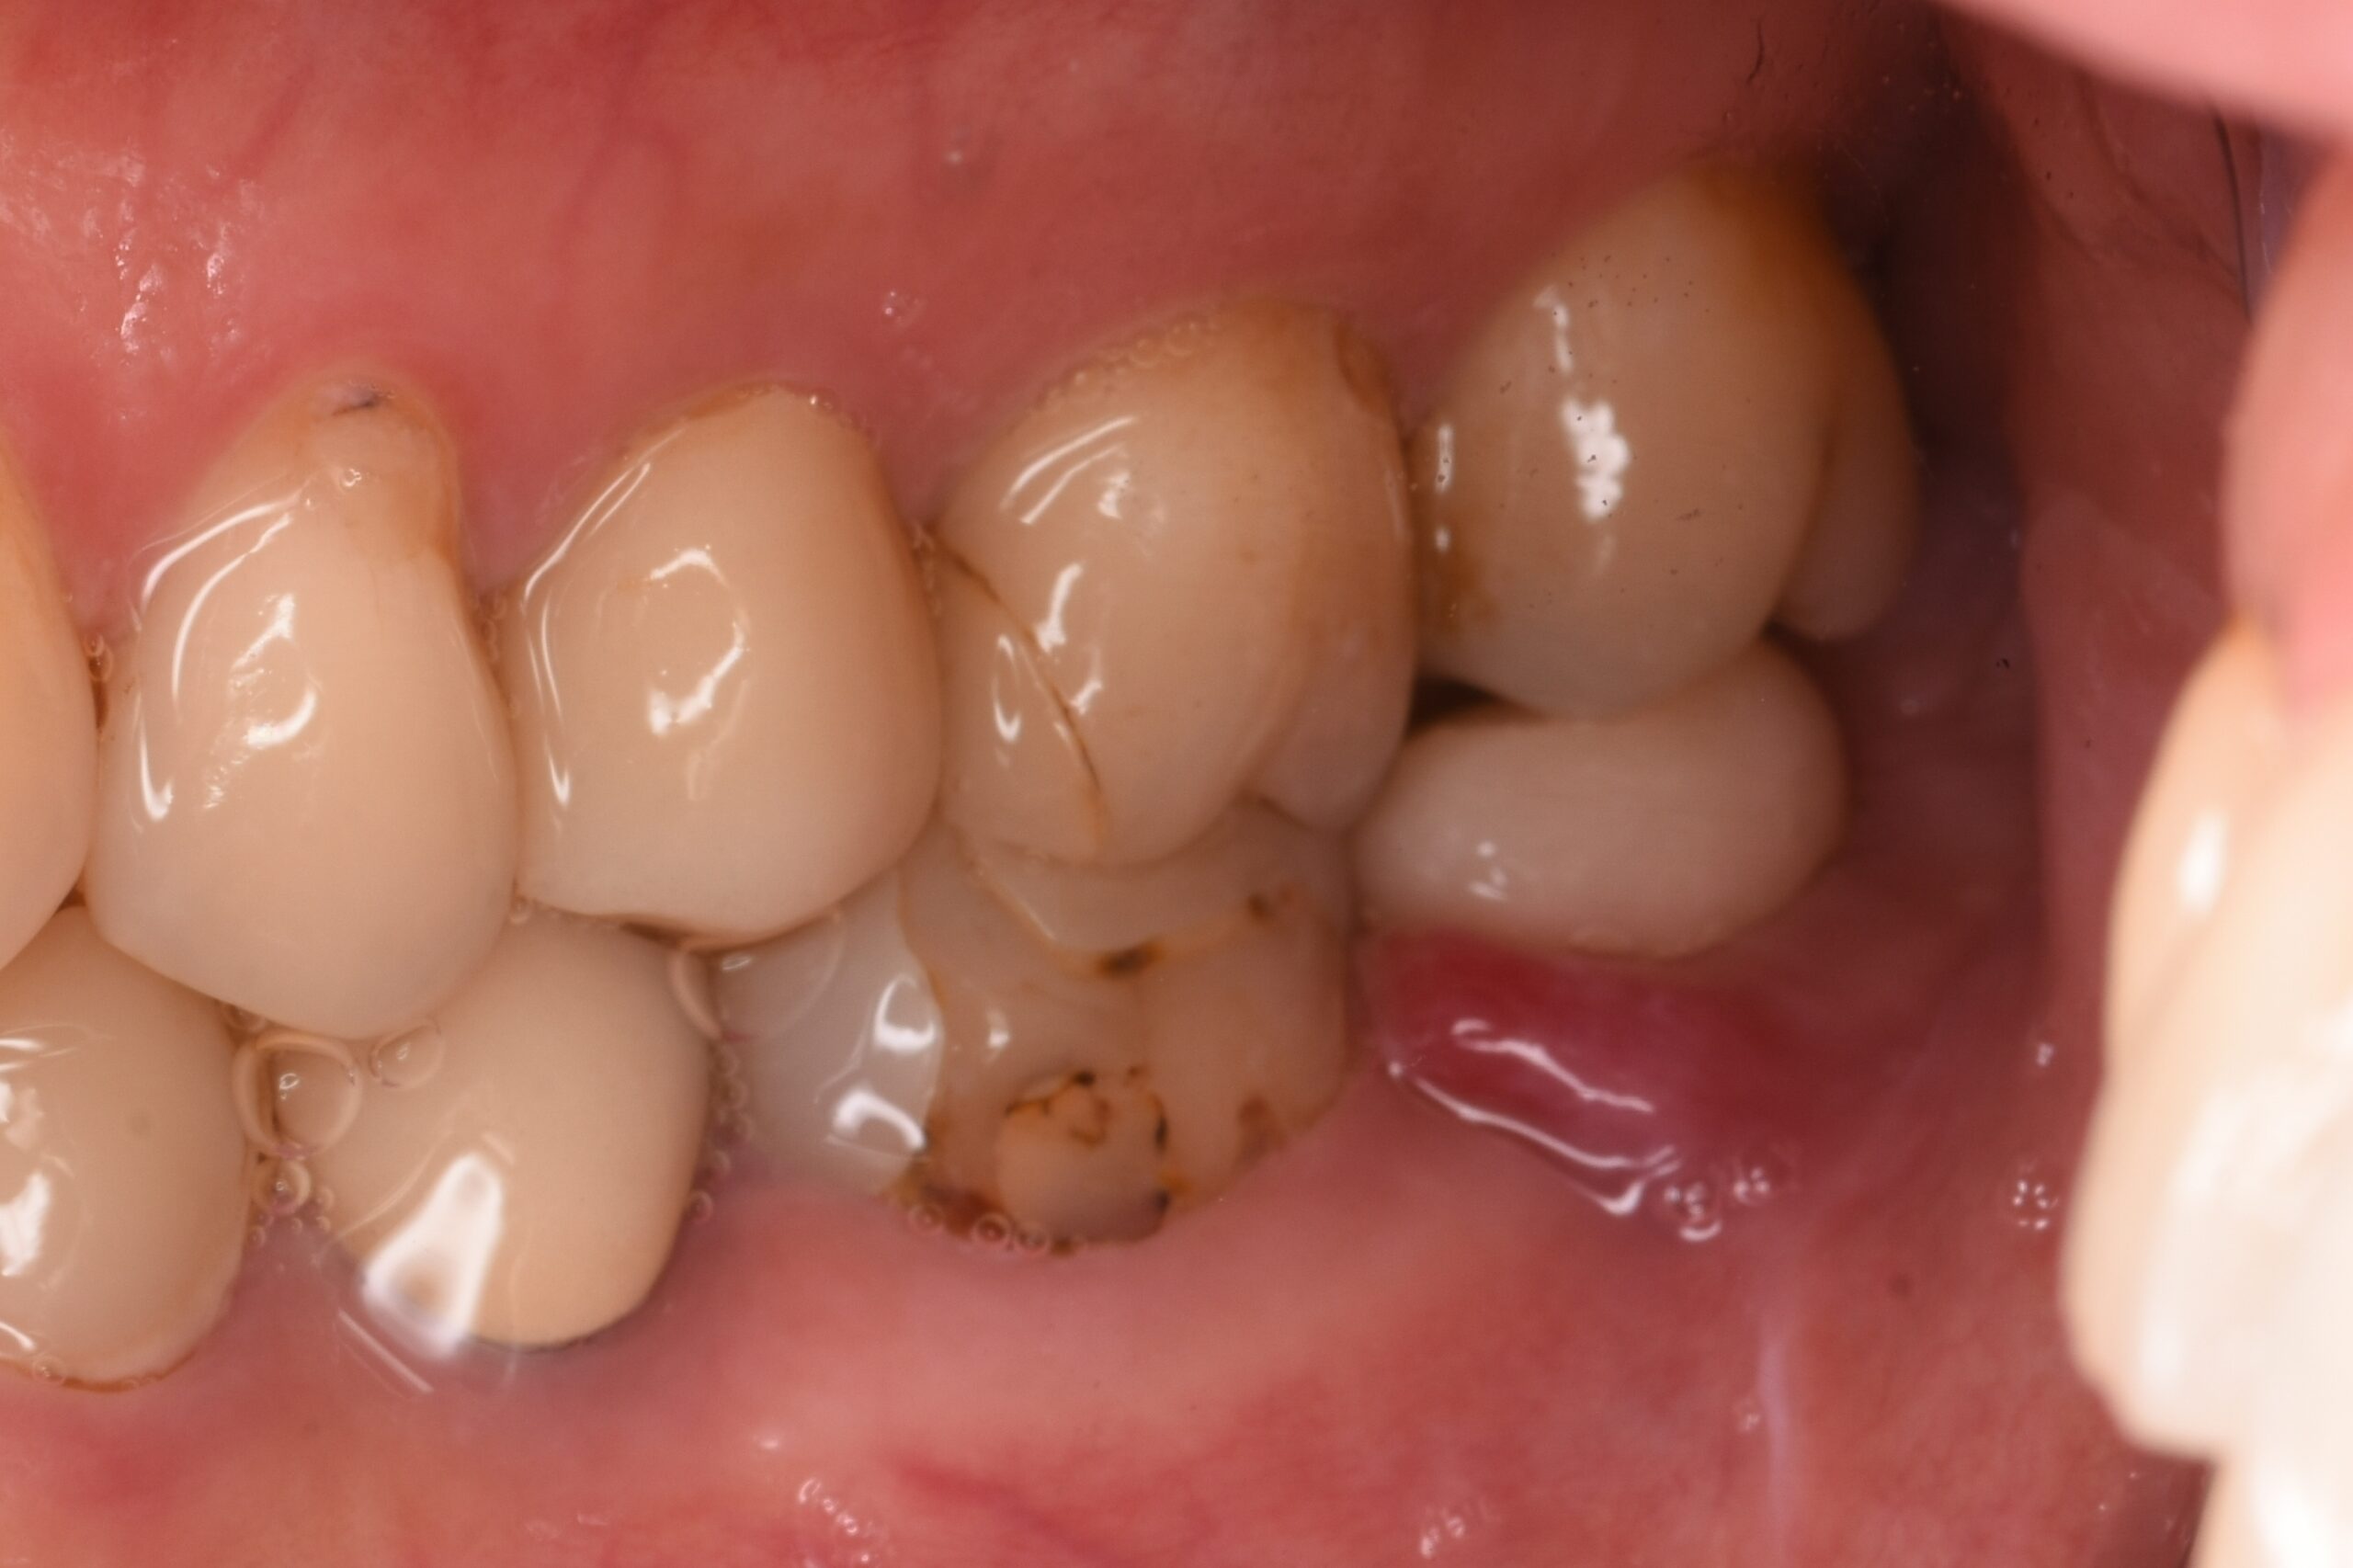

• before

歯肉の腫れの原因である感染した歯の神経や細菌を取り除くため、根管治療を行いました。

左下奥歯の腫れ、噛むと痛みがある

左下第二小臼歯・第二大臼歯 根尖性歯周炎